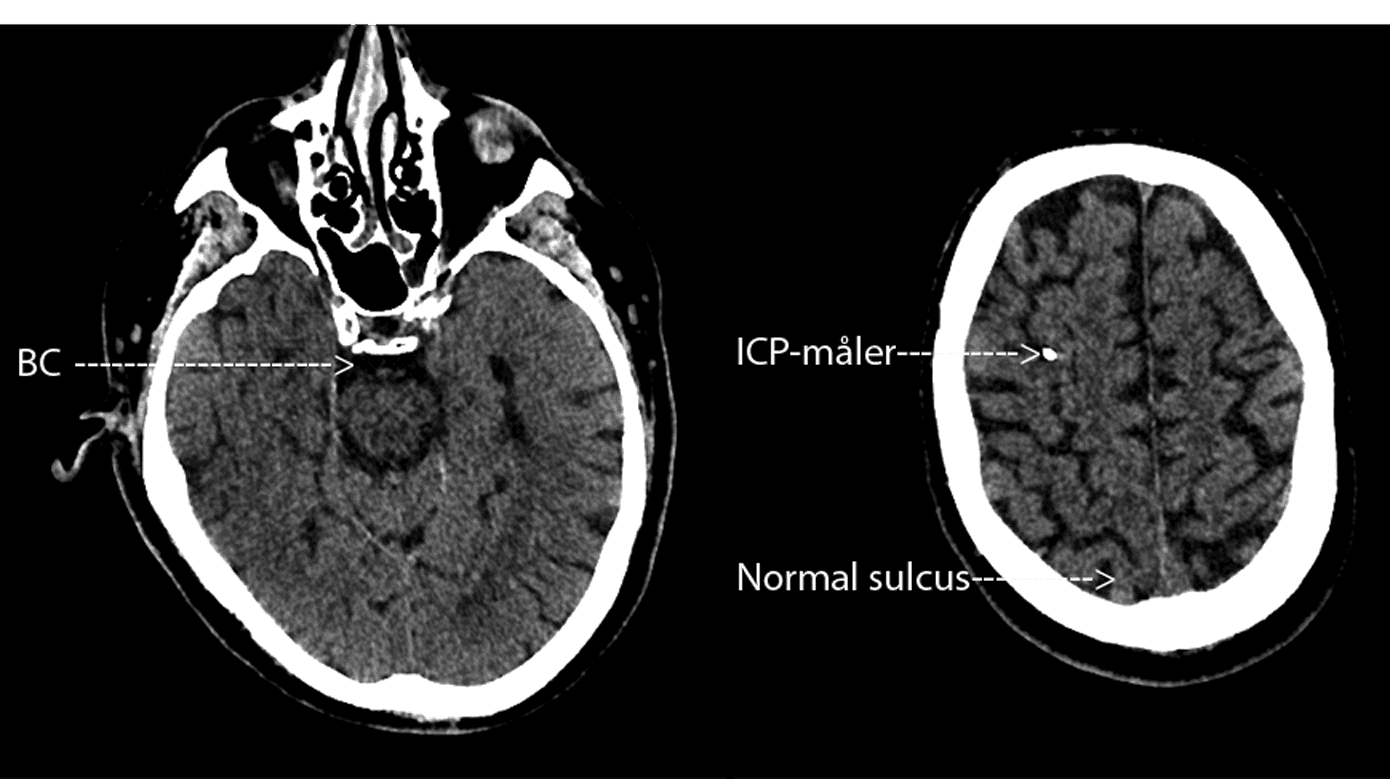

Rutinemæssig CT af cerebrum (CT-C) ved mistanke om ABM er ikke indiceret, da den ofte vil være normal [14, 22]. Derimod er CT-C indiceret ved nedsat bevidsthedsniveau, fokale neurologiske udfald, inklusive kranienervepåvirkning af enhver type, samt kramper [23]. Patienter med ABM visiteret til intensivafdelingen har en højere forekomst af patologisk CT-C med fund af diffust ødem, hydrocefalus og infarkter eller blødninger hos enkelte [1, 2, 16]. Dog er det væsentligt, at i det tidlige forløb af ABM kan ICP være svært forhøjet trods normal CT-C (Figur 1) [1, 6, 24].